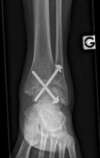

arthrose primitive de cheville

arthrodèse de cheville par vissage en croix